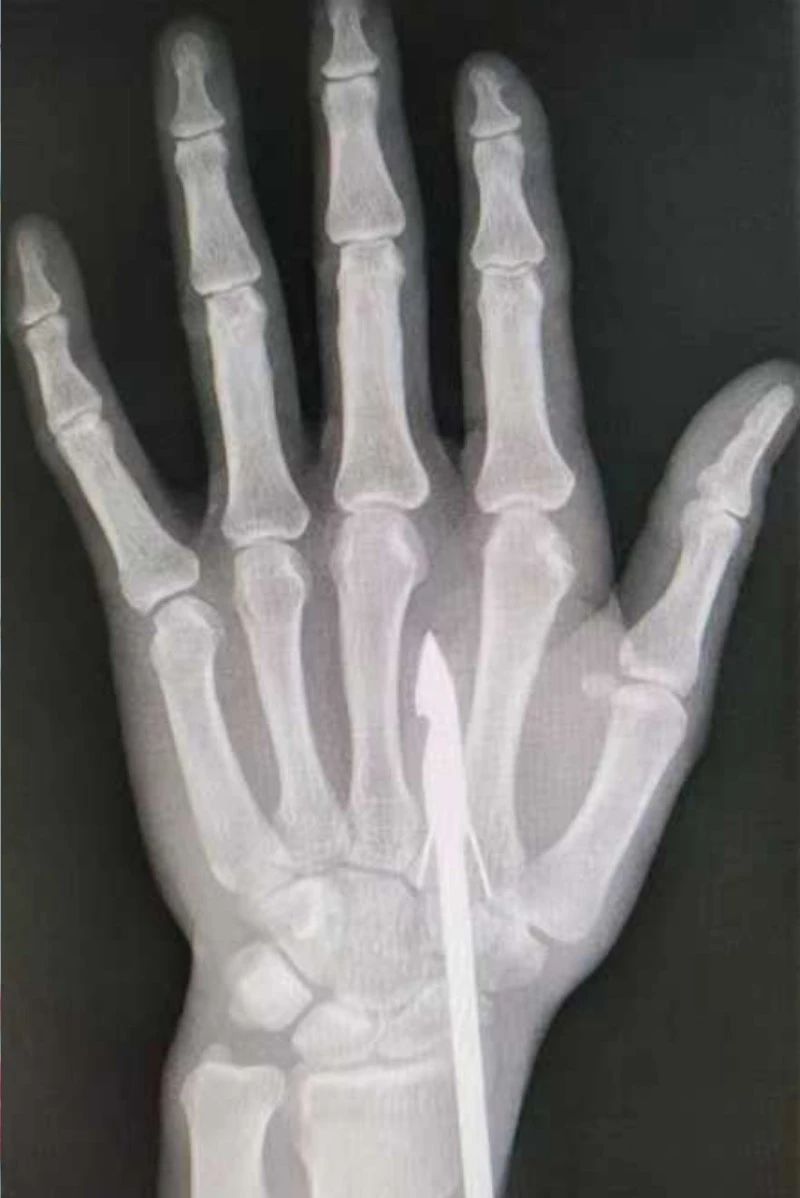

時(shí)間緊迫,每一秒的流逝都可能對(duì)傷者的手部功能造成不可逆的損害。接診醫(yī)生代彭威,迅速對(duì)傷者進(jìn)行了初步檢查。他注意到,魚(yú)鉤已經(jīng)深深嵌入皮膚,情況遠(yuǎn)比表面看起來(lái)復(fù)雜。沒(méi)有絲毫猶豫,立即安排了X線(xiàn)檢查以確認(rèn)魚(yú)鉤的位置及傷及范圍,以及急診化驗(yàn)檢查以評(píng)估患者的整體狀況。

確保在取出魚(yú)鉤的同時(shí),不對(duì)周?chē)慕M織造成額外的傷害。8點(diǎn)15分左右患者在局部浸潤(rùn)麻下進(jìn)行手術(shù),經(jīng)探查后魚(yú)鉤未傷及重要血管、神經(jīng)及肌腱,經(jīng)過(guò)緊張的十分鐘,魚(yú)鉤終于被順利取出,隨后對(duì)傷口進(jìn)行了仔細(xì)的清理和縫合,用敷料仔細(xì)包扎,確保傷口能夠順利愈合。